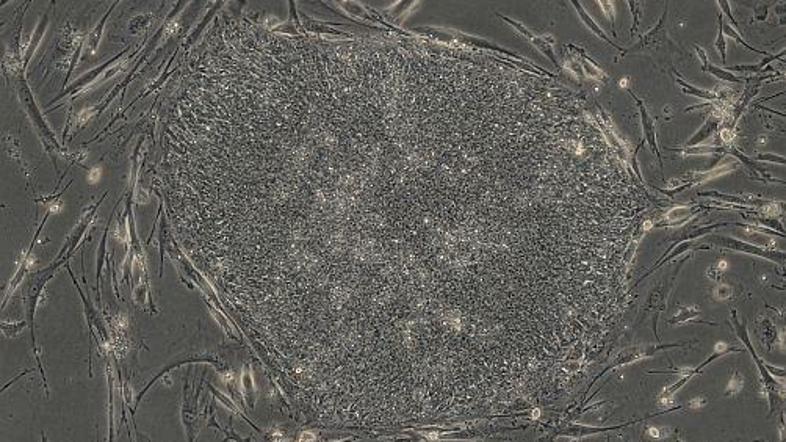

Fotografija prikazuje genetske spremembe kožnih celic, ki so se posrečile znanst Žurnal24 main

Znanstvenikom je uspelo kožne celice človeka reprogramirati v izvorne celice in tako ustvariti katerokoli celično tkivo človeškega telesa.

Za uspeh sta zaslužni ekipi ameriških in japonskih znanstvenikov. Slednjim je uspelo s pomočjo kemikalijskega koktajla, ki je vseboval štiri proteine za nadzor genov, spremeniti fibroblaste odraslega človeka (kožne celice, ki jih je lahko vzgajati) v kateregakoli od 220 tipov celic v človekovem telesu. Tako dobljene celice so bile podobne, a ne identične izvornim, znanstveniki pa so iz njih naredili možgansko in srčno tkivo. Po dvanajstih dneh rasti tkiva v laboratoriju je tako nastala srčna mišica, ki je začela tudi biti.